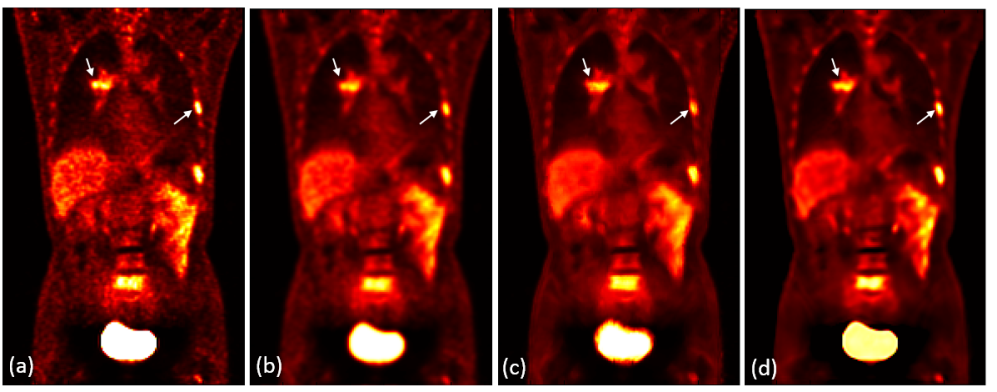

3.3 Clinical PET image denoising

Refer to caption

(a)

Figure 7: Coronal view of (a) original noisy PET image; (b) post-filtered image using a Gaussian filter with FWHM = 1 pixel; (c) post-filtered image using NLM with CT images and window size set to 5×5×55555\times 5\times 5; (d) post-filtered image using the proposed method trained with 700 epochs. Lesions are pointed out using arrows.